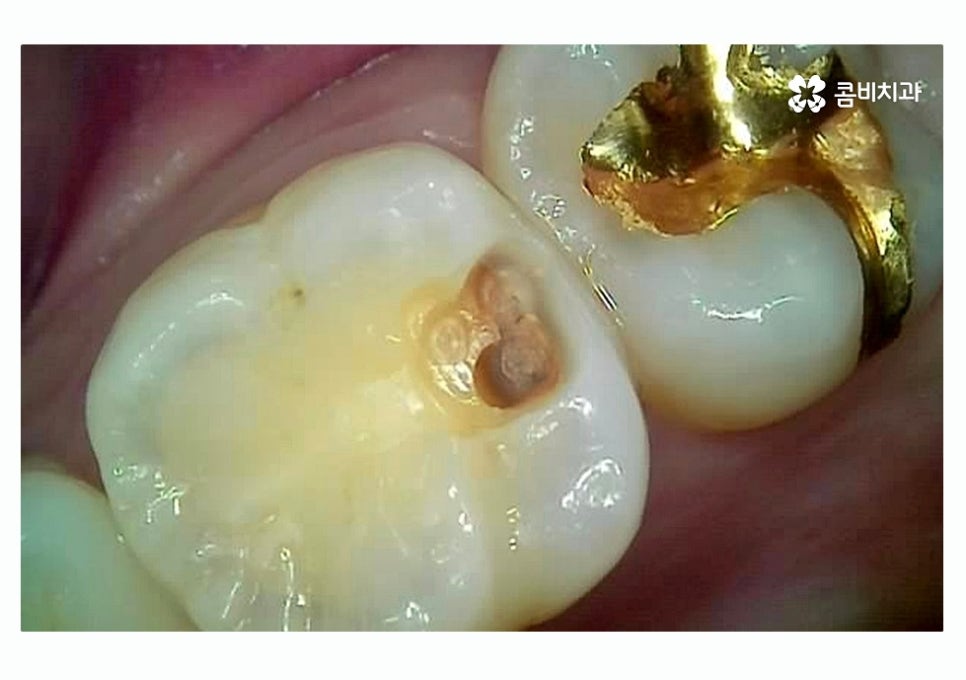

성인의 경우 충치 발생률 자체는 줄어들 수 있지만

이미 충치 떼우기 한 부위의 내부 혹은 인접면에서

충치가 발생하는 경우 초기에는 증상이 나타나지 않고,

이미 증상이 발생한 경우에는 충치가 많이 진행되어

치아의 손상 범위가 클 수 있는데요.

이러한 충치 유형은 통증을 느끼기 전에 눈으로는

파악이 어렵다는 점에서 주기적으로 치과에

가서 검진을 받지 않는다면 조기 발견이 어려울 수 있어요.

치아의 인접면은 충치 떼우기 자체가 쉽지 않은 부위에

속하며 치아 양측이 함께 썩거나 치아의 뿌리 근처가

상하는 경우도 많기 때문에 평소 음식물이 치아 사이에

낀 채로 방치되지 않도록 각별한 주의가 필요할 수 있어요.